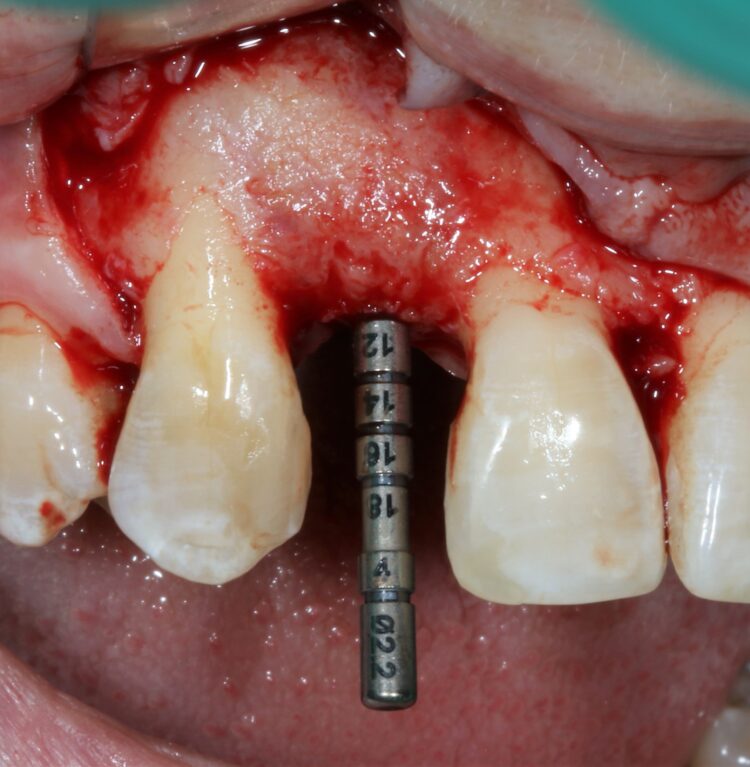

The first treatment phase included the elevation of a large full thickness flap to fully expose the area and enable the harvesting of autogenous bone utilising a safescraper.

The UR2 was then removed including excavation of all granulation tissue, taking care to avoid any direct curettage of the exposed UR3 root. The large bone defect was then filled with a 50/50 mix of autogenous bone chips and an allograft (MinerOss®, a cortico-cancellous mix – BioHorizons Camlog) and the buccal defect was covered with a native porcine collagen membrane with a high percentage of collagen type III for a prolonged barrier function of six months. No fixation pins were used.

The second surgery involved a palatal crestal incision and a full thickness flap elevation revealing good turnover of bone graft into host bone. A bone level implant was placed in an appropriate three-dimensional position completely surrounded by new bone and no additional bone grafting was required. A 4mm healing cap was placed.